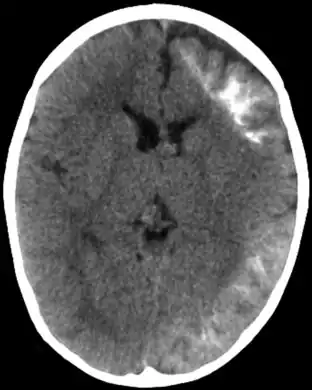

A Síndrome de Sturge-Weber, às vezes chamada angiomatose encefalotrigeminal, é uma doença extremamente rara, congênita, neurológica e também é uma desordem de pele. É uma facomatose, e é freqüentemente associada com glaucomas, manchas de coloração vinhosa, ataques apopléticos, retardamento mental e angioma leptomeningeal ipsilateral. É causada por uma má-formação artério-venosa que acontece num dos hemisférios do cérebro, do mesmo lado dos sinais físicos descritos acima. Normalmente, só um lado da cabeça é afetado.

Também há má formação de vasos sanguíneos na pia-máter do cérebro, do mesmo lado da cabeça que a marca de nascença. Isto causa calcificação do tecido e perda de células do nervo no córtex cerebral.